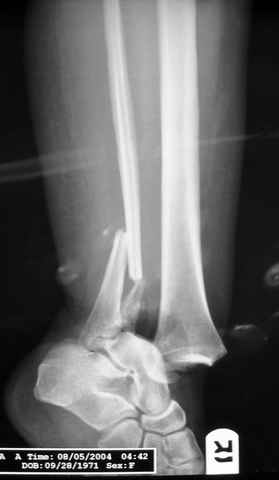

Pilon fracture:

конец малоберцевой кости, к нему прикрепляется латеральный суставной фрагмент дистального эпиметафиза большеберцовой кости (как на снимке)

и таранная кость, которые при репозиции малоберцовой кости репонируются автоматически.